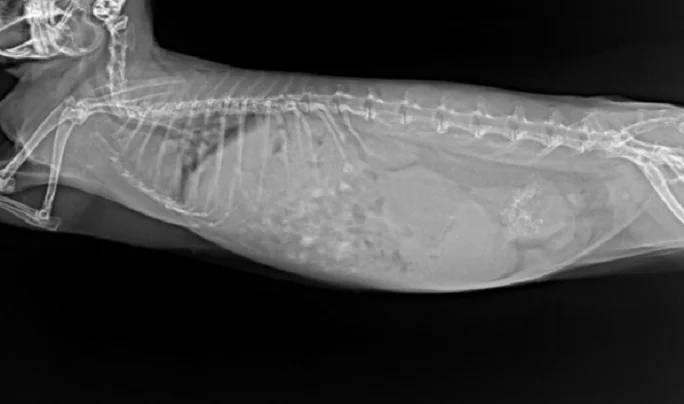

Рентген крольчихи 7 лет. Аденокарцинома матки с метастазами в легкие

- Рентгенограммы брюшной полости — можно обнаружить в каудальной части брюшной полости, как правило, дорсальнее мочевого пузыря;

- Рентгенограммы грудной клетки – для оценки наличия метастазов;